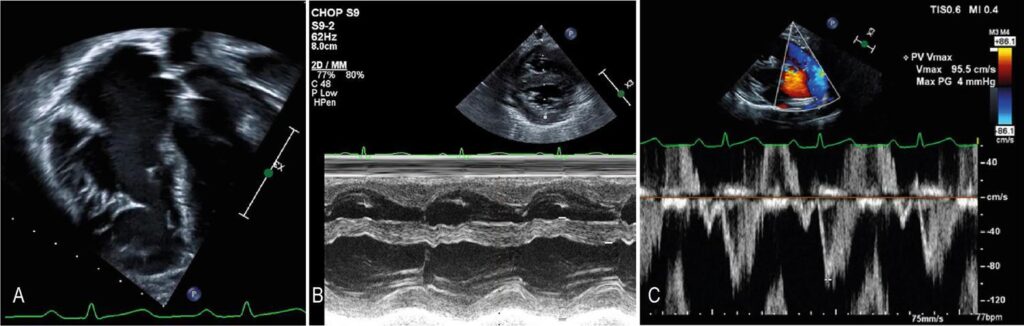

On the apical four-chamber view, I examine the motion of the tricuspid valve toward the apex (measured as the tricuspid annular plane systolic excursion [TAPSE] as detailed below) and the motion of the RV wall toward the septum versus data of prior studies. Likewise, parasternal long- and short-axis views are important. In those with favorable acoustic windows, RV wall shortening can be assessed using M-mode ( ). It is worth noting that the qualitative assessment of RV function should not be the sole parameter. ,